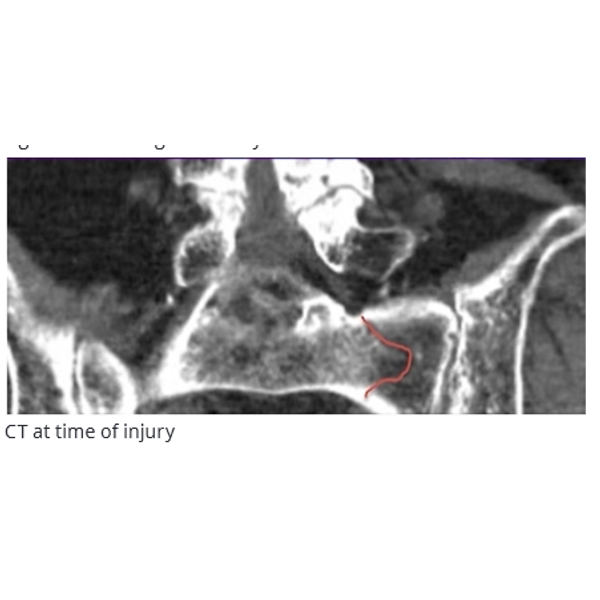

A 70-year-old female had a ground-level fall. Computed tomography imaging showed sacral insufficiency fractures in the left ala. No lumbar fracture was observed. Conservative treatment was initiated but the patient was referred 6 weeks post injury, unable to mobilize with a walker and needing a wheelchair. There was no anterior pelvic pain with palpation or weight bearing, but disabling left posterior pain with any weight bearing, and pain at rest and when rolling in bed. Prior to the injury, the patient was a community ambulator; typically with a cane and occasionally with a walker. The patient had osteoporosis, hepatic failure with

cirrhosis, and moderate obesity.